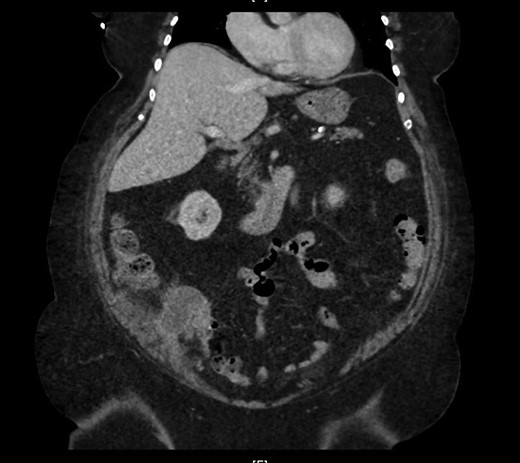

The patient had a previous admission 4 weeks back with the same kind of complaint, but according to the patient, went for an outpatient follow-up upon with her OB/GYN doctor. Upon presentation with at the outpatient department, with the wage ongoing right-sided discomfort for few weeks, the physician placed an order for a computerized tomography (CT) scan which identified a mass-like density in the base of the cecum with extra luminal soft tissue thickening and probable developing phlegmon (Fig. 1) not yet percutaneously drainable measuring (47 × 37 mm). She was advised to go to the emergency department. During the admission, she spent 5 days in the hospital as an inpatient and was treated for a phlegmonous abscess of the appendix, as per the CT indicated. During the hospital course, she was treated with Flagyl 500 mg IV TID and Aztronam 1 g TID for 5 days and, during discharge, she was given PO Flagyl Q8H and PO Bactrim Q12 H for another 9 days. She was advised to follow-up with the surgical outpatient services to schedule an interval appendectomy with the resolution of the inflammation. She soon developed a recurrent episode of abdominal pain, starting 3 weeks post-discharge and was re-admitted with worsening reproduction of the prior symptoms.

Cross section of abdominal computed tomography showed an appendiceal tumor.

CT scan of the abdomen revealed stable soft tissue focus and adjacent rim of enhancing low-density collection along the posteromedial and posterior aspects of the cecum in the right lower abdomen (Fig. 2). Suggestive of the possibility of chronic infectious or neoplastic etiologies of appendicular origin. The appendix was not visualized as a separate structure. Comparison of the previous CT excluded worsening of the intra-abdominal or intra-pelvic process. Upon discussion with medical and surgical teams, reproduction of symptoms and CT evidence, aided the direction for surgical intervention. On the second day of hospital admission, surgical laparoscopy located the terminal ileum with adhesions from the sidewall. The findings included perforated viscus and mass at the appendicular base. With this appearance, a direct intervention was impossible, we proceeded with hand-assisted partial cecectomy, appendectomy and removed the entire mass.

Marked appendiceal wall swelling and intraluminal filling defect of contrast medium over appendix noted in the coronal CT-image.